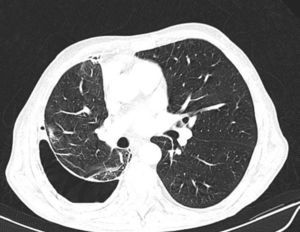

Tomografía computarizada de tóraxComo se ha mencionado anteriormente, los pacientes con un PPA o un PA tienen un engrosamiento de la pleura visceral. Sin embargo, es muy difícil observarlo en la radiografía de tórax, o incluso en la TC convencional, ya que su grosor suele ser de menos de 3mm. Para poder demostrarlo, Huggins et al. sugieren llevar a cabo lo que ellos denominan una TC con contraste de aire (fig. 3). La técnica consiste en realizar un neumotórax durante la manometría pleural a los pacientes que cumplan los siguientes criterios: aparición de una PP (menor de –25cmH2O) y exclusión —por la historia clínica y el análisis del líquido pleural— de una malignidad o de una inflamación pleural activa. La realización del neumotórax permite, por una parte, poner de manifiesto el engrosamiento de la pleura visceral y, por otra, poder seguir drenando líquido, si fuera necesario, y aliviar el dolor torácico generado por unas presiones excesivamente negativas. El procedimiento consiste en abrir una llave del circuito del manómetro para permitir la entrada de aire al espacio pleural hasta alcanzar presiones intrapleurales fisiológicas (presión media del líquido pleural de –5cmH2O). Este procedimiento solo puede realizarse bajo la monitorización y uso de un manómetro digital. Aun así, la demostración de un engrosamiento pleural, la persistencia de un neumotórax en condiciones de PP negativas y una PEL elevada, en ausencia de otras causas de PNE, establece la presencia de unas condiciones mecánicas consistentes —pero no diagnósticas— de un PA13.